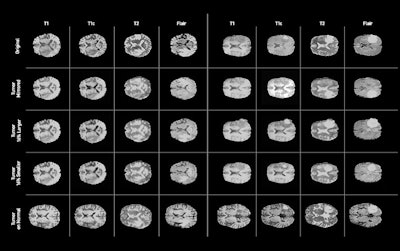

The algorithm allows developers to alter the size of a tumor on the MR image, change its location, or place it on an otherwise normal brain -- enabling hundreds or even thousands of these synthetic images to be created, according to the researchers. In testing, they found that adding synthetic data to augment real MRI data improved the performance of a deep-learning algorithm.